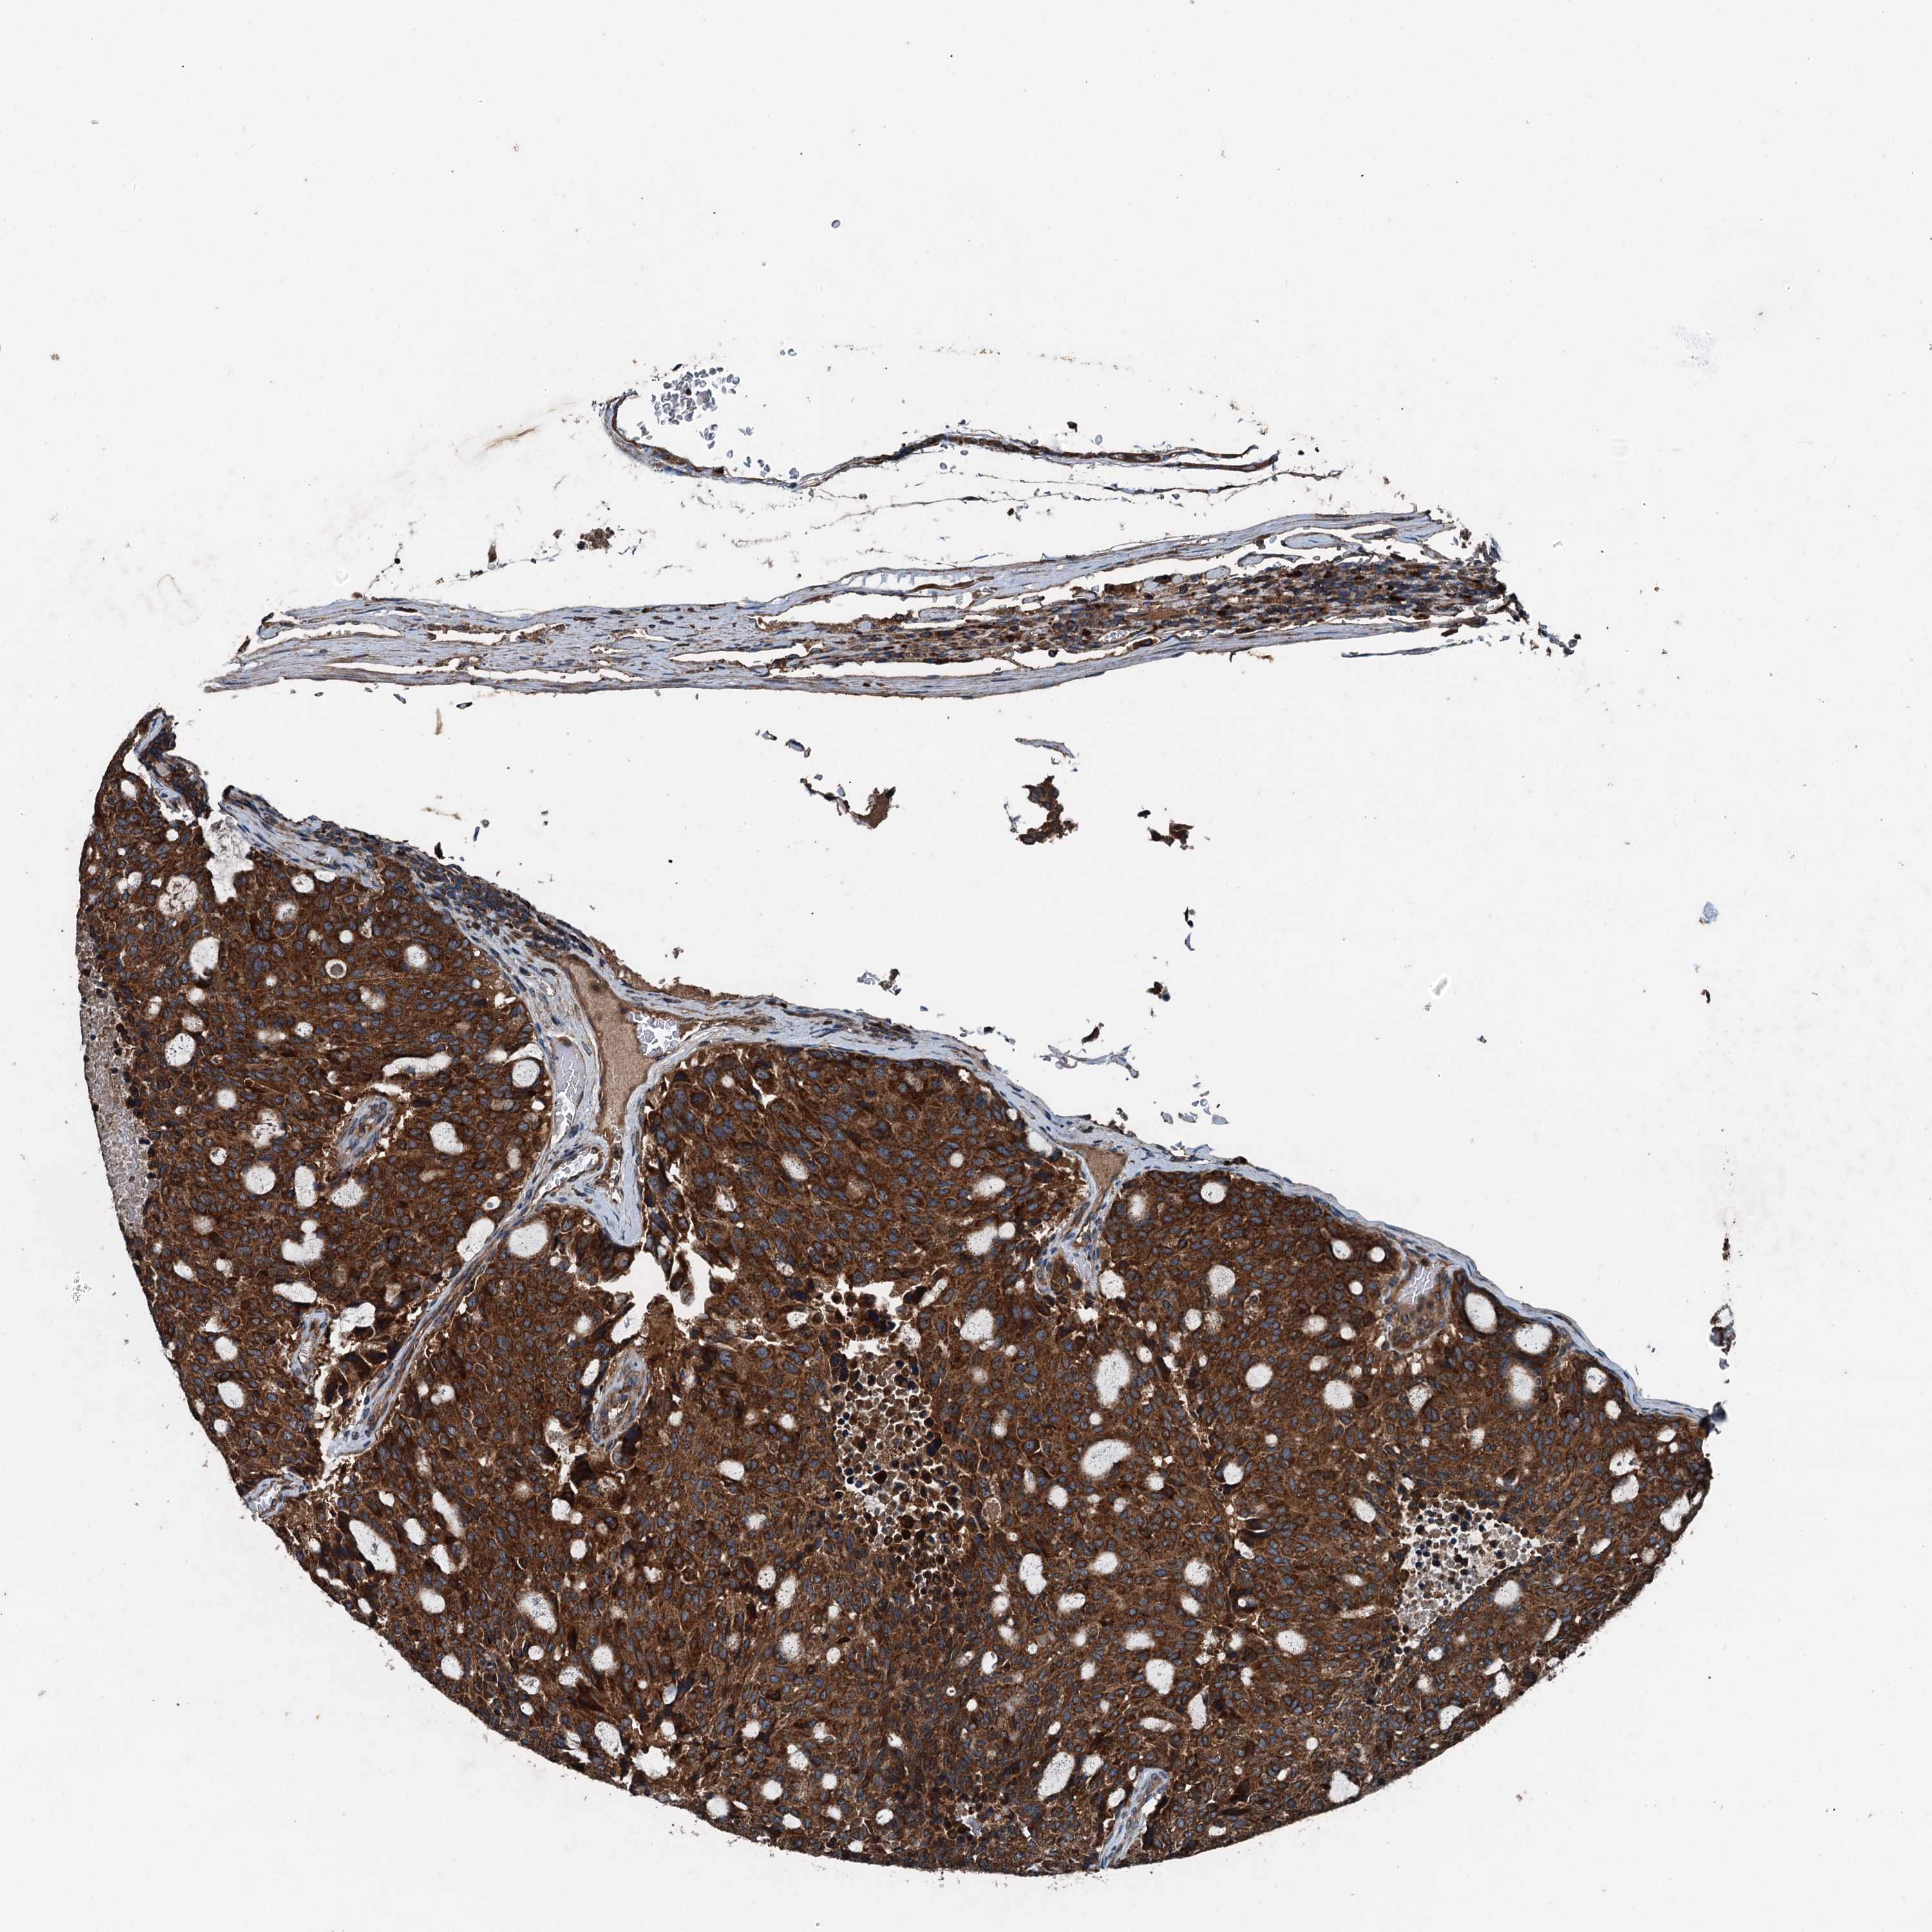

CARCINOID - Protein expressioni

A mouse-over function shows sample information and annotation data. Click on an image to view it in a full screen mode. Samples can be filtered based on level of antibody staining by selecting one or several of the following categories: high, medium, low and not detected. The assay and annotation is described here.

Antibody stainingi

Antibody staining in the annotated cell types in the current human tissue is reported as not detected, low, medium, or high, based on conventional immunohistochemistry profiling in selected tissues. This score is based on the combination of the staining intensity and fraction of stained cells.

Each image is clickable and will lead to virtual microscopy that enables deeper exploration of all samples and also displays staining intensity scores, fraction scores and subcellular localization as well as patient and tissue information for each sample.

Antibody HPA041227

Staining

High

Medium

Low

Not detected

Intensity

Strong

Moderate

Weak

Negative

Quantity

>75%

75%-25%

<25%

None

Location

Nuclear

Cytoplasmic/membranous

Cytoplasmic/membranous,nuclear

Carcinoid, malignant, NOS

Carcinoma, NOS